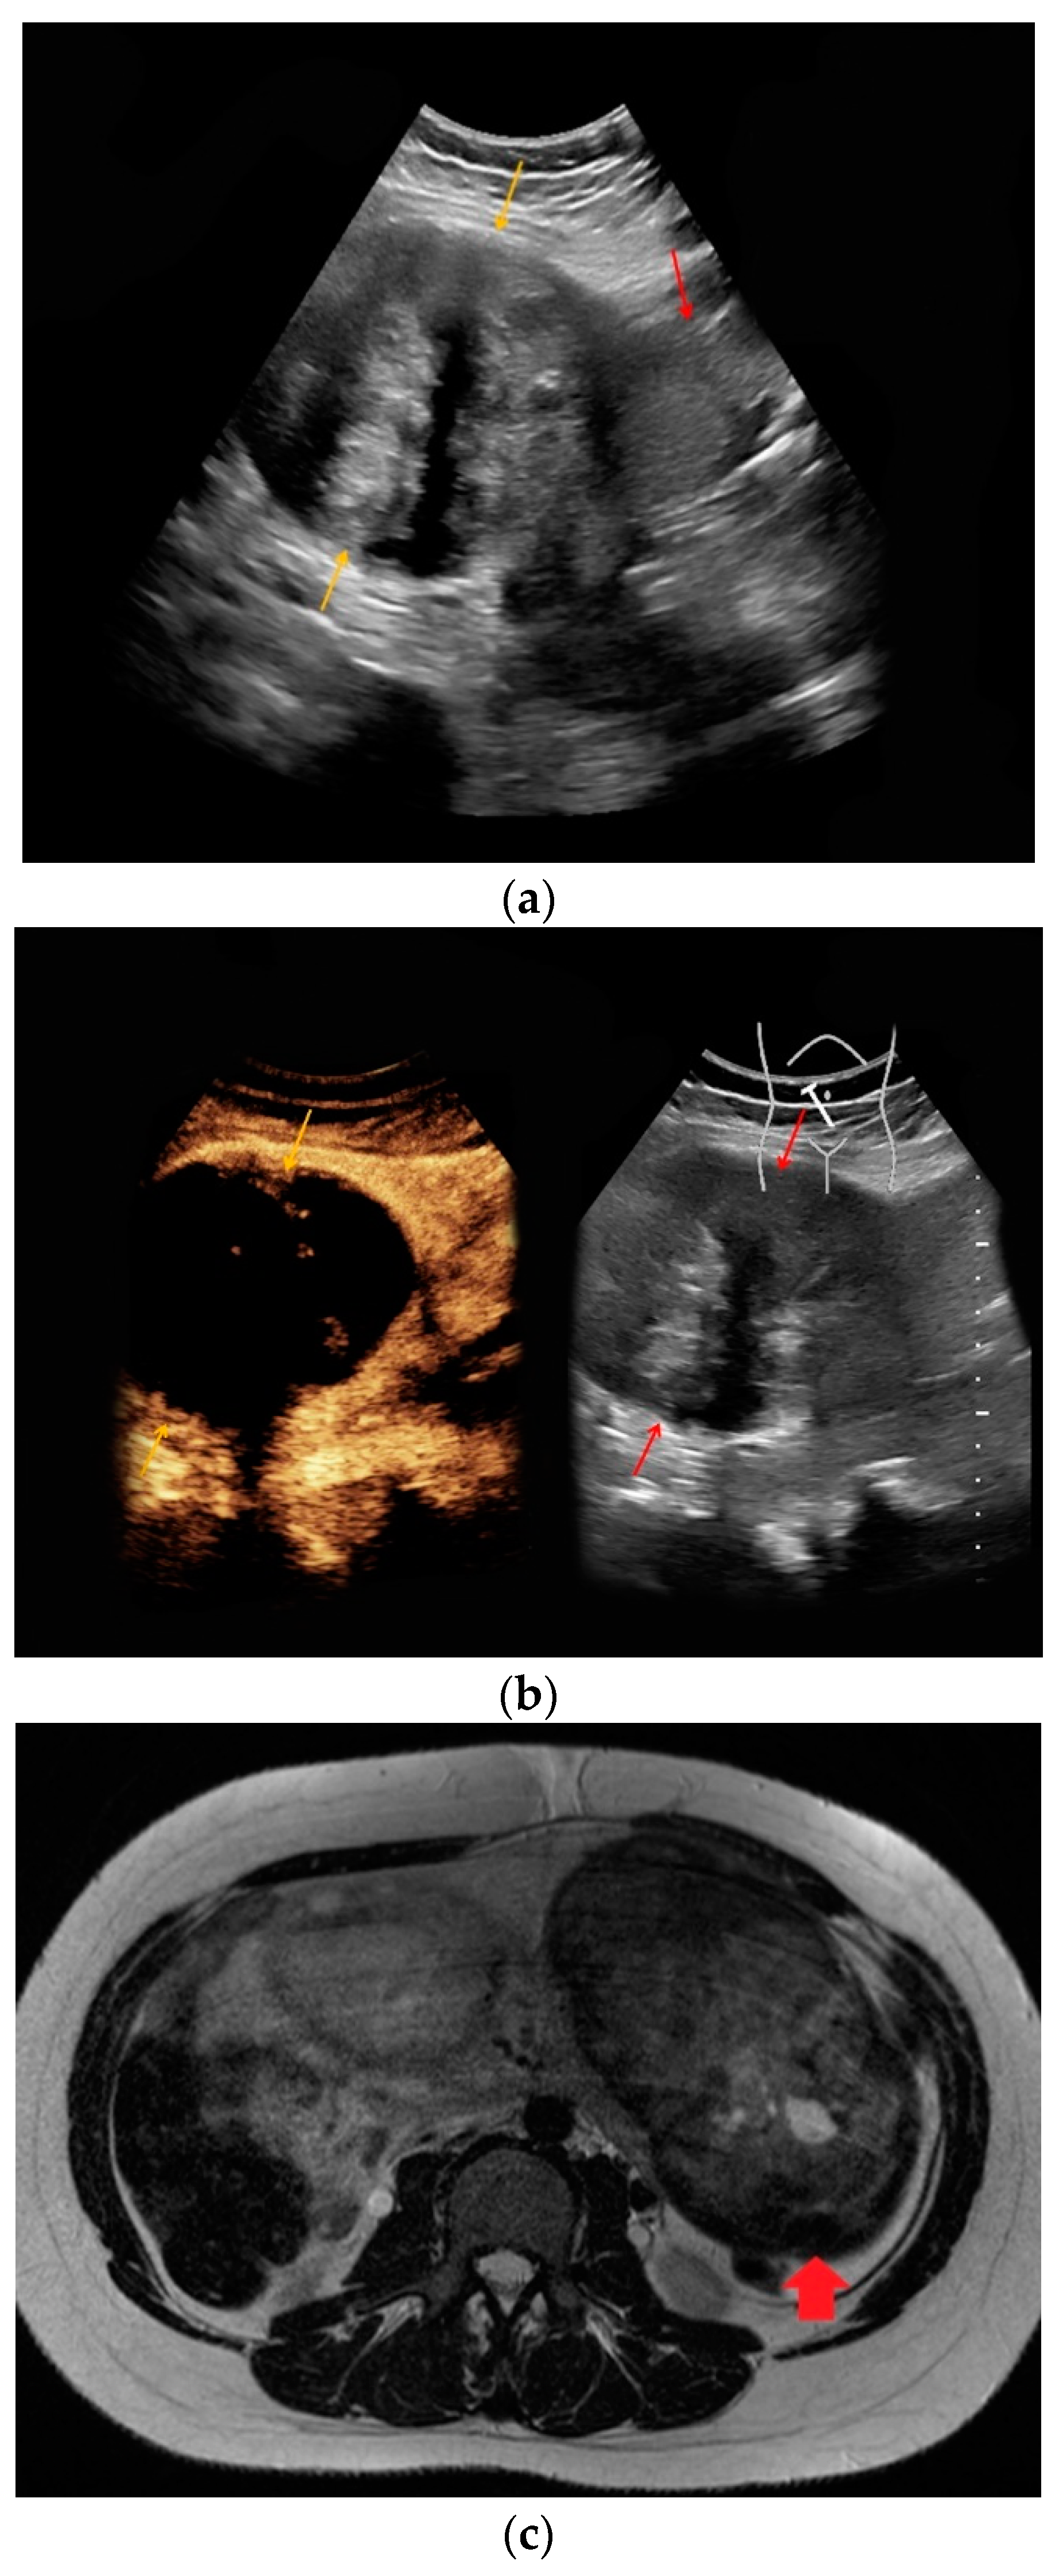

| #3 | 34 | 25 | Necrotic uterine fibroid | B-mode: inhomogeneous, hypo-/hyperechoic, 15 cm Doppler: no hypervascularization CEUS: slight contrast enhancement | inhomogeneous, predominantly T1-hypointense, T2-hypointense |